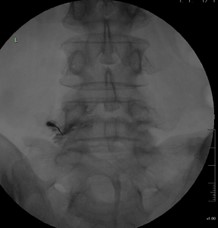

検査

当院では、術前の診断精度を高める目的で、神経根ブロック(左)やCTミエログラフィー(右)検査を行っています。検査後は、経過を確認する目的で1泊入院となりますが、翌日には退院が可能です。